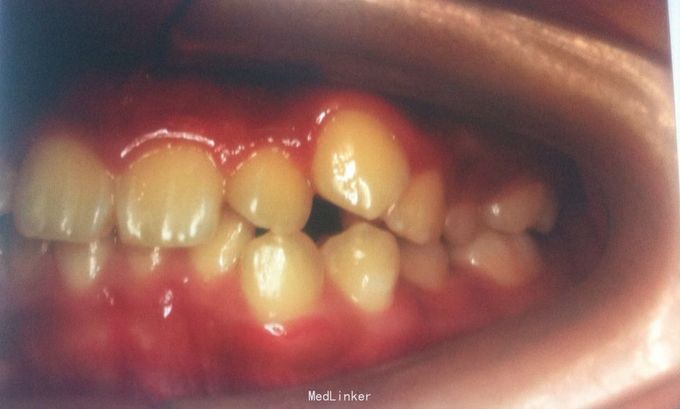

恒牙期 33,44唇侧错位 磨牙中性关系 前牙覆合2度、覆盖1度 牙列拥挤

牙列拥挤、安氏一类 拔牙矫治,拔除14、24、34、44(强支抗)排齐整平上下牙列,直丝弓矫治器,关闭拔牙间隙,矫治后前牙覆合覆盖正常,磨牙中性关系,面型略改善